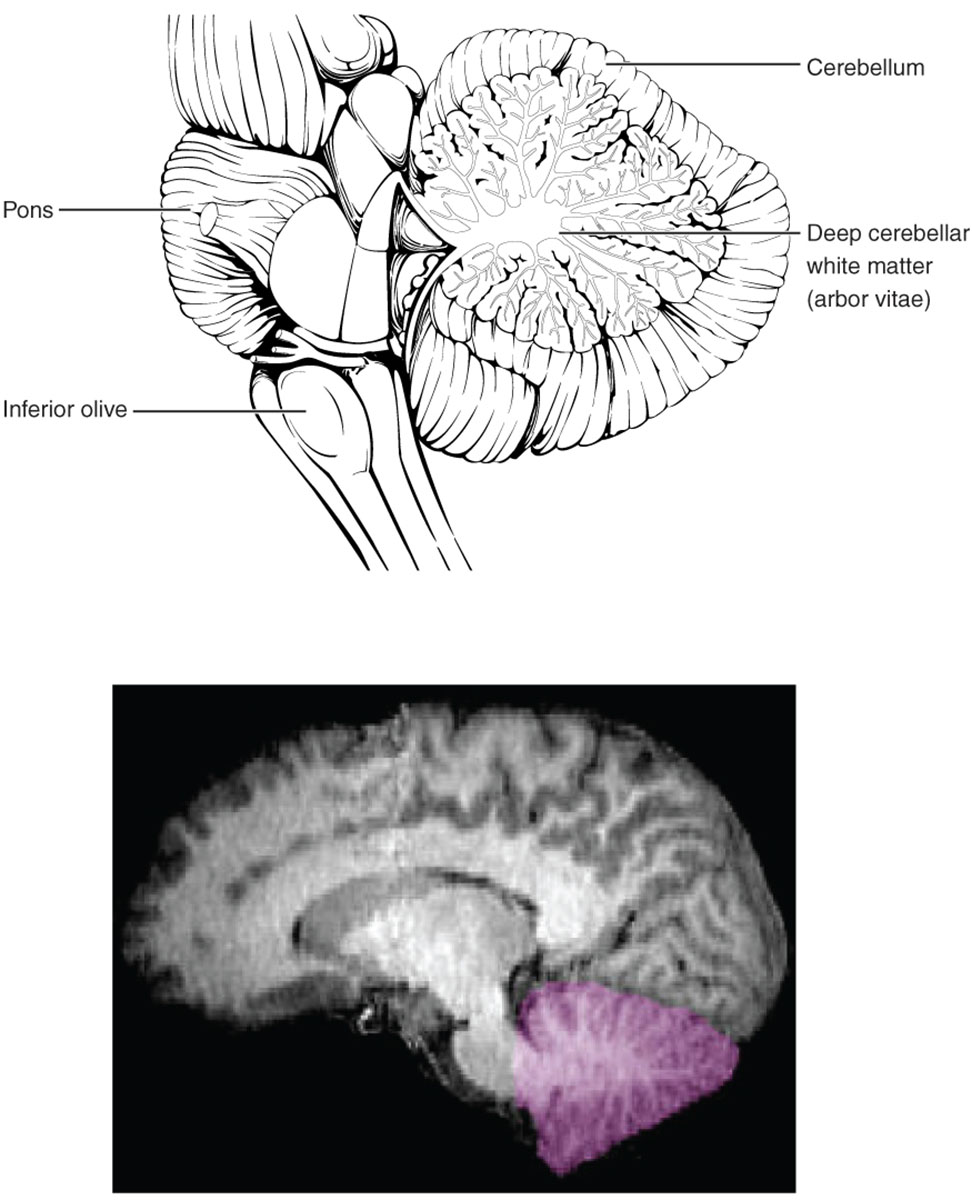

The cerebellum, a key component of the hindbrain, plays an essential role in coordinating movement, balance, and motor learning. This image presents a detailed anatomical illustration of the cerebellum alongside an imaging view, highlighting structures such as the cerebellum, pons, inferior olive, and deep cerebellar white matter (arbor vitae), which facilitate sensory input and output pathways. Exploring these elements offers a comprehensive understanding of cerebellar function and its integration with the brain stem.

The cerebellum is located posterior to the brain stem and is responsible for fine-tuning motor activities, maintaining posture, and contributing to cognitive processes like attention and language. Its folded structure, known as folia, increases surface area for neural processing, receiving inputs from the spinal cord and cerebral cortex via the pons and inferior olive.

The pons serves as a bridge between the midbrain and medulla, relaying signals from the cerebral cortex to the cerebellum through large white matter tracts. It also houses nuclei for cranial nerves involved in facial sensation and movement, supporting respiratory rhythm and arousal.

The inferior olive, a nucleus in the medulla, provides climbing fiber inputs to the cerebellum, crucial for motor learning and error correction. These fibers synapse on Purkinje cells, influencing cerebellar output to refine movements and adapt to new tasks.

The deep cerebellar white matter, resembling a tree-like structure called arbor vitae, consists of myelinated axons that connect cerebellar cortex to deep nuclei and external pathways. This branching pattern facilitates efficient communication between cerebellar regions, enabling coordinated signal transmission for balance and precision.

The accompanying imaging view highlights the cerebellum in purple, demonstrating its appearance in neuroimaging. Such visuals aid in identifying structural details non-invasively.

- The highlighted region emphasizes the vermis, central to axial posture, and hemispheres for appendicular control.